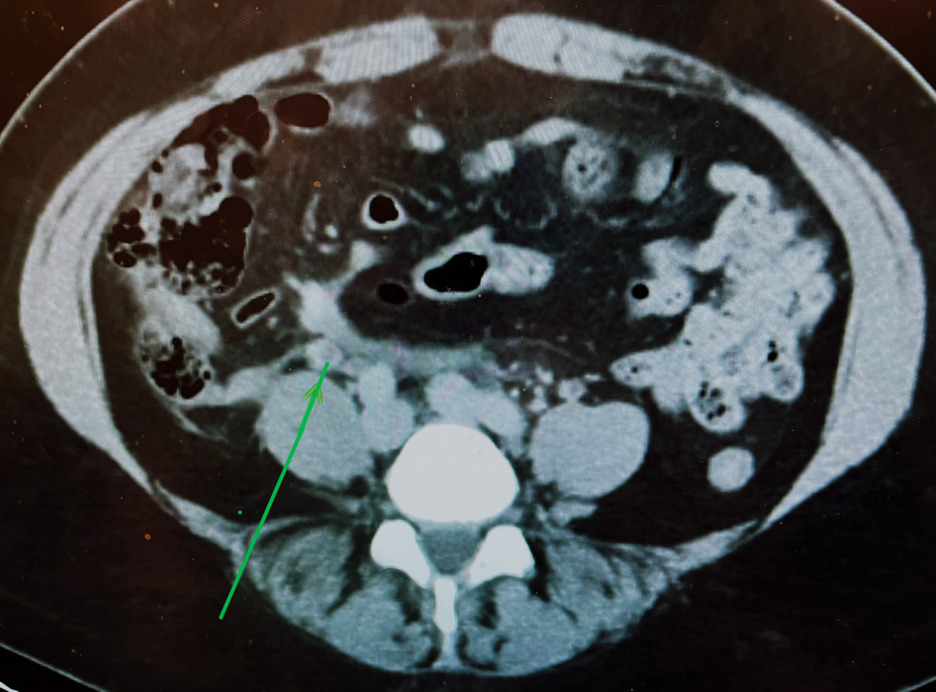

Computed tomography (CT) scan of her abdomen and pelvis with intravenous (IV) contrast was performed and showed an enlarged uterus (fourteen weeks) with multiple intramural and some submucosal leiomyomas. Mild fat stranding and haziness was seen in the right retroperitoneal area with a partial thrombosis of the right mid gonadal vein (Figure 1, arrow). Our consulting hematologist recommended treating her GVT with full anticoagulation with low molecular weight heparin (LMWH) in the post-operative setting for seven days to reduce the risk of embolization. The risk/benefit of starting a direct oral anticoagulant (DOAC) were discussed with the patient, and she was started on Apixaban, 5mg twice daily for a duration of three months with close outpatient follow-up. She saw her primary care doctor two weeks after her discharge from hospital and all symptoms had resolved.

The pathophysiology of GVT in this case, like any other DVT, is attributed to the co-occurrence of endothelial disruption, venous stasis, and hypercoagulability (Virchow’s Triad).6 The symptoms of the GVT can be challenging to distinguish from other intra-abdominal pathology. Imaging plays an important role in the diagnosis. Pelvic ultrasound is usually the first line imaging modality, but accuracy of imaging obtained by ultrasound is limited by the patients’ body habitus, bowel gas pattern and/or the operators’ skill. Computed Tomography (CT) or Magnetic Resonance Imaging (MRI) with contrast may be more accurate for clinching the diagnosis, but there is currently no gold standard test. In this case, we postulated that the fat stranding and haziness seen in the right retroperitoneal area was procedure related inflammation. Furthermore, it is likely that the procedure itself, with the embolization of so many uterine fibroids (fifteen), could have produced the degree of inflammation to account for her symptoms on presentation. When added to the transient hypercoagulability and post procedure immobilization the cascade leading to venous thrombosis likely occurred. Although rare, this partial GVT had the potential to progress and ultimately embolise to the lung.7 Our clinical decision to treat her was based on the higher risk of pulmonary embolism versus the potential side effects of anticoagulation. In patients with gonadal vein thrombosis, it is also recommended that localized malignancy be ruled out which it was in this case.